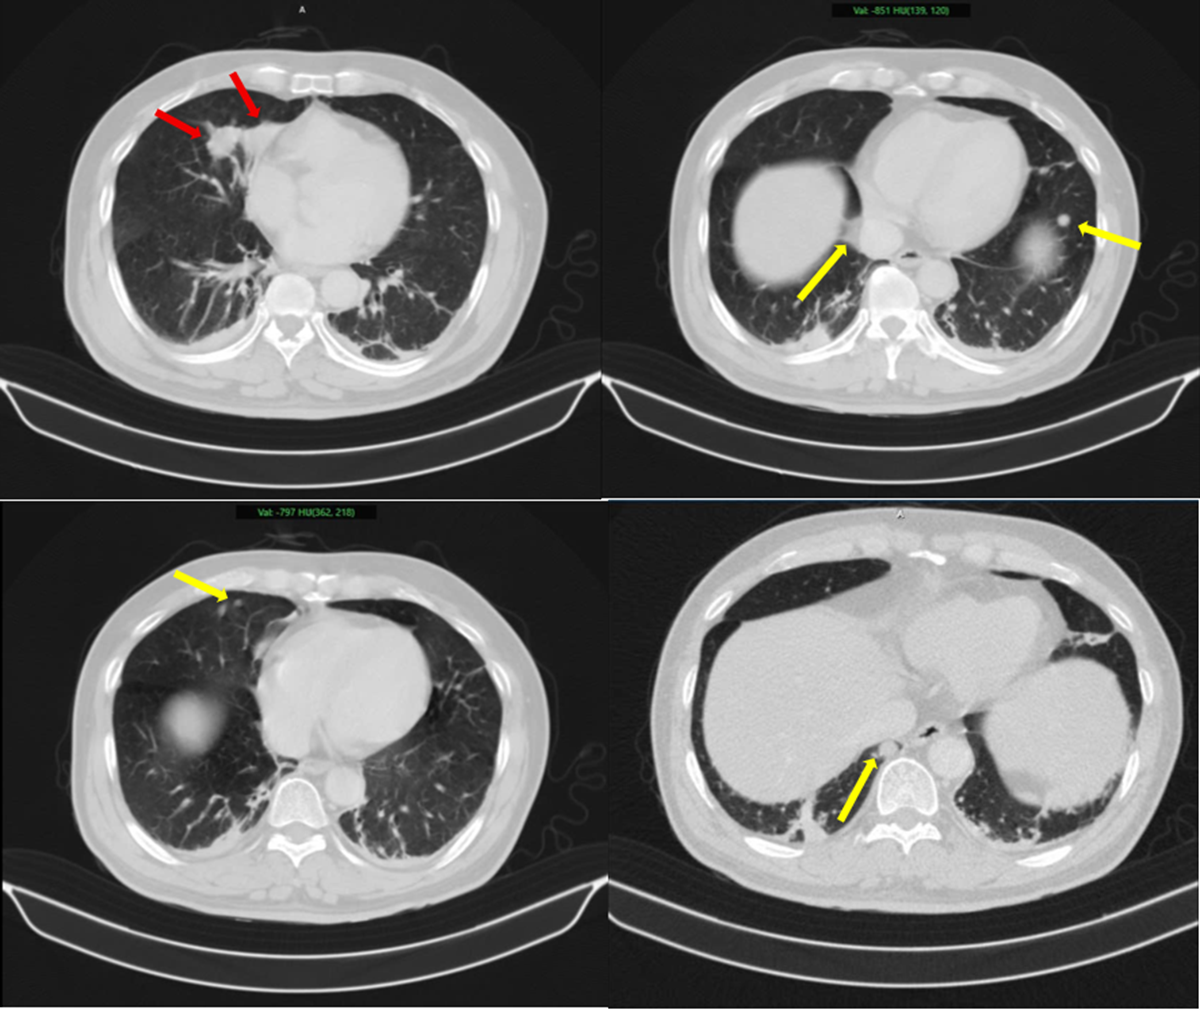

Hình ảnh 2 khối u bờ đa cung ở nhu mô thùy giữa phổi phải, dính vào màng phổi trung thất (mũi tên đỏ) kèm nhiều nốt đặc nhỏ rải rác nhu mô phổi hai bên (mũi tên vàng) gợi ý tổn thương thứ phát. Ảnh: BV Bạch Mai.

Tại viện kết quả sinh thiết và phân tích mô bệnh học kết hợp hóa mô miễn dịch giúp làm rõ: khối u phổi là ung thư biểu mô tuyến của phổi, trong khi khối u tuyến tiền liệt là ung thư biểu mô tuyến với điểm Gleason 9 - thuộc nhóm nguy cơ cao. Hai loại ung thư này có nguồn gốc hoàn toàn khác nhau, không phải di căn chéo.